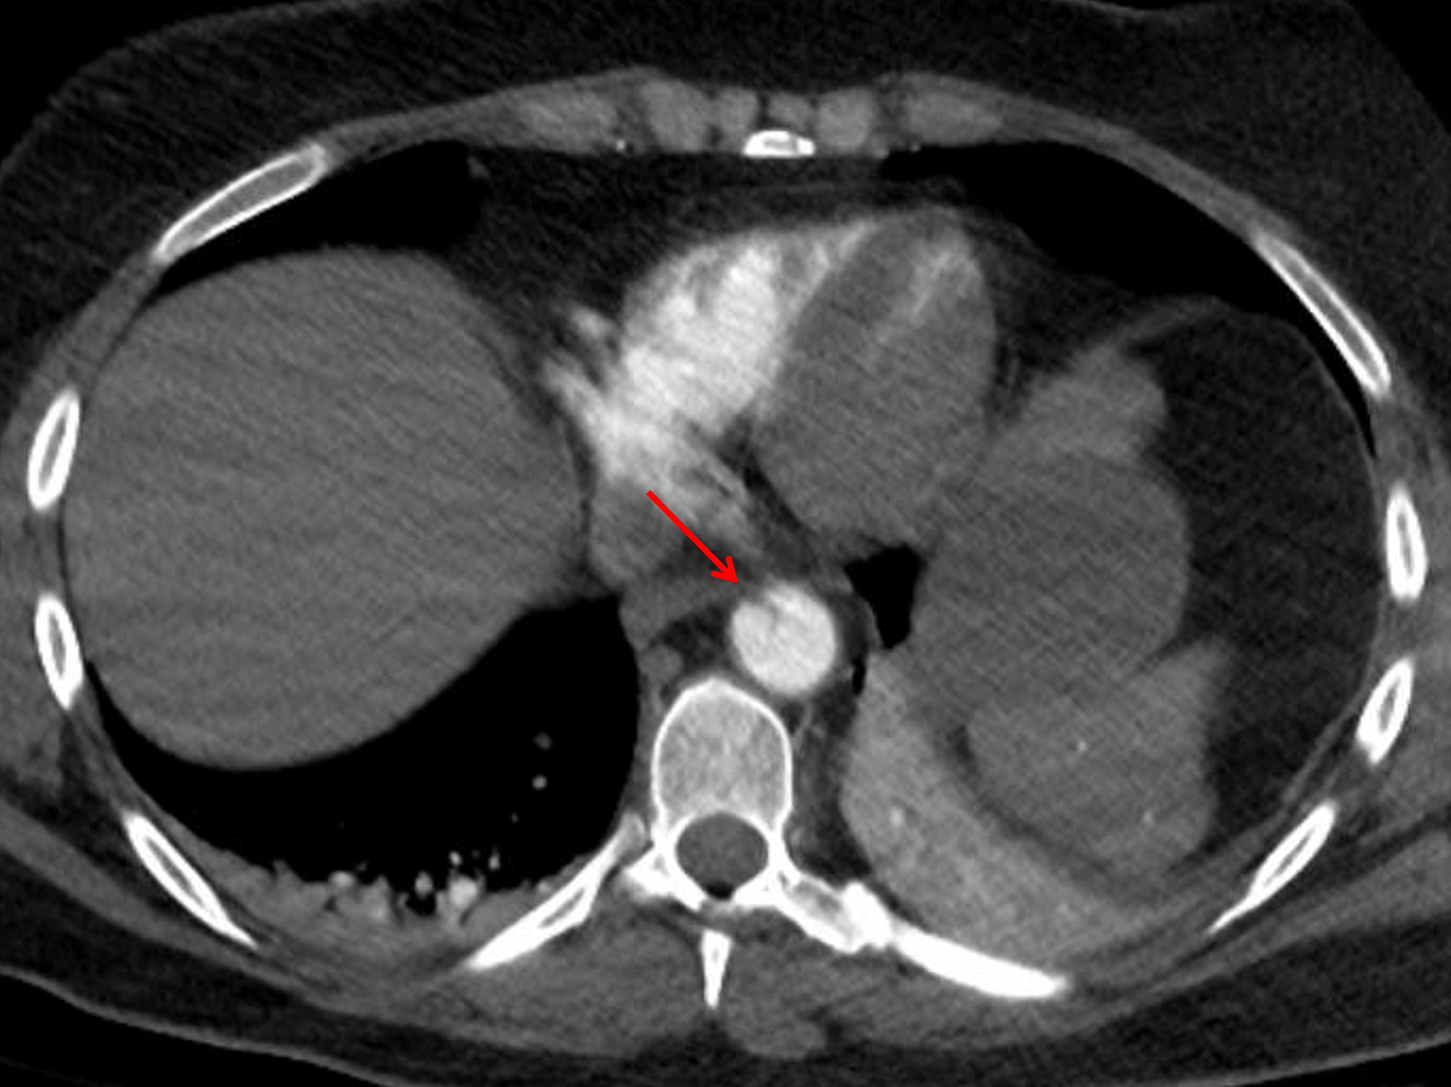

Age: 50

Sex: Female

Indication: Trauma

Mild acute traumatic aortic injury near the diaphragmatic hiatus without surrounding hemorrhage.